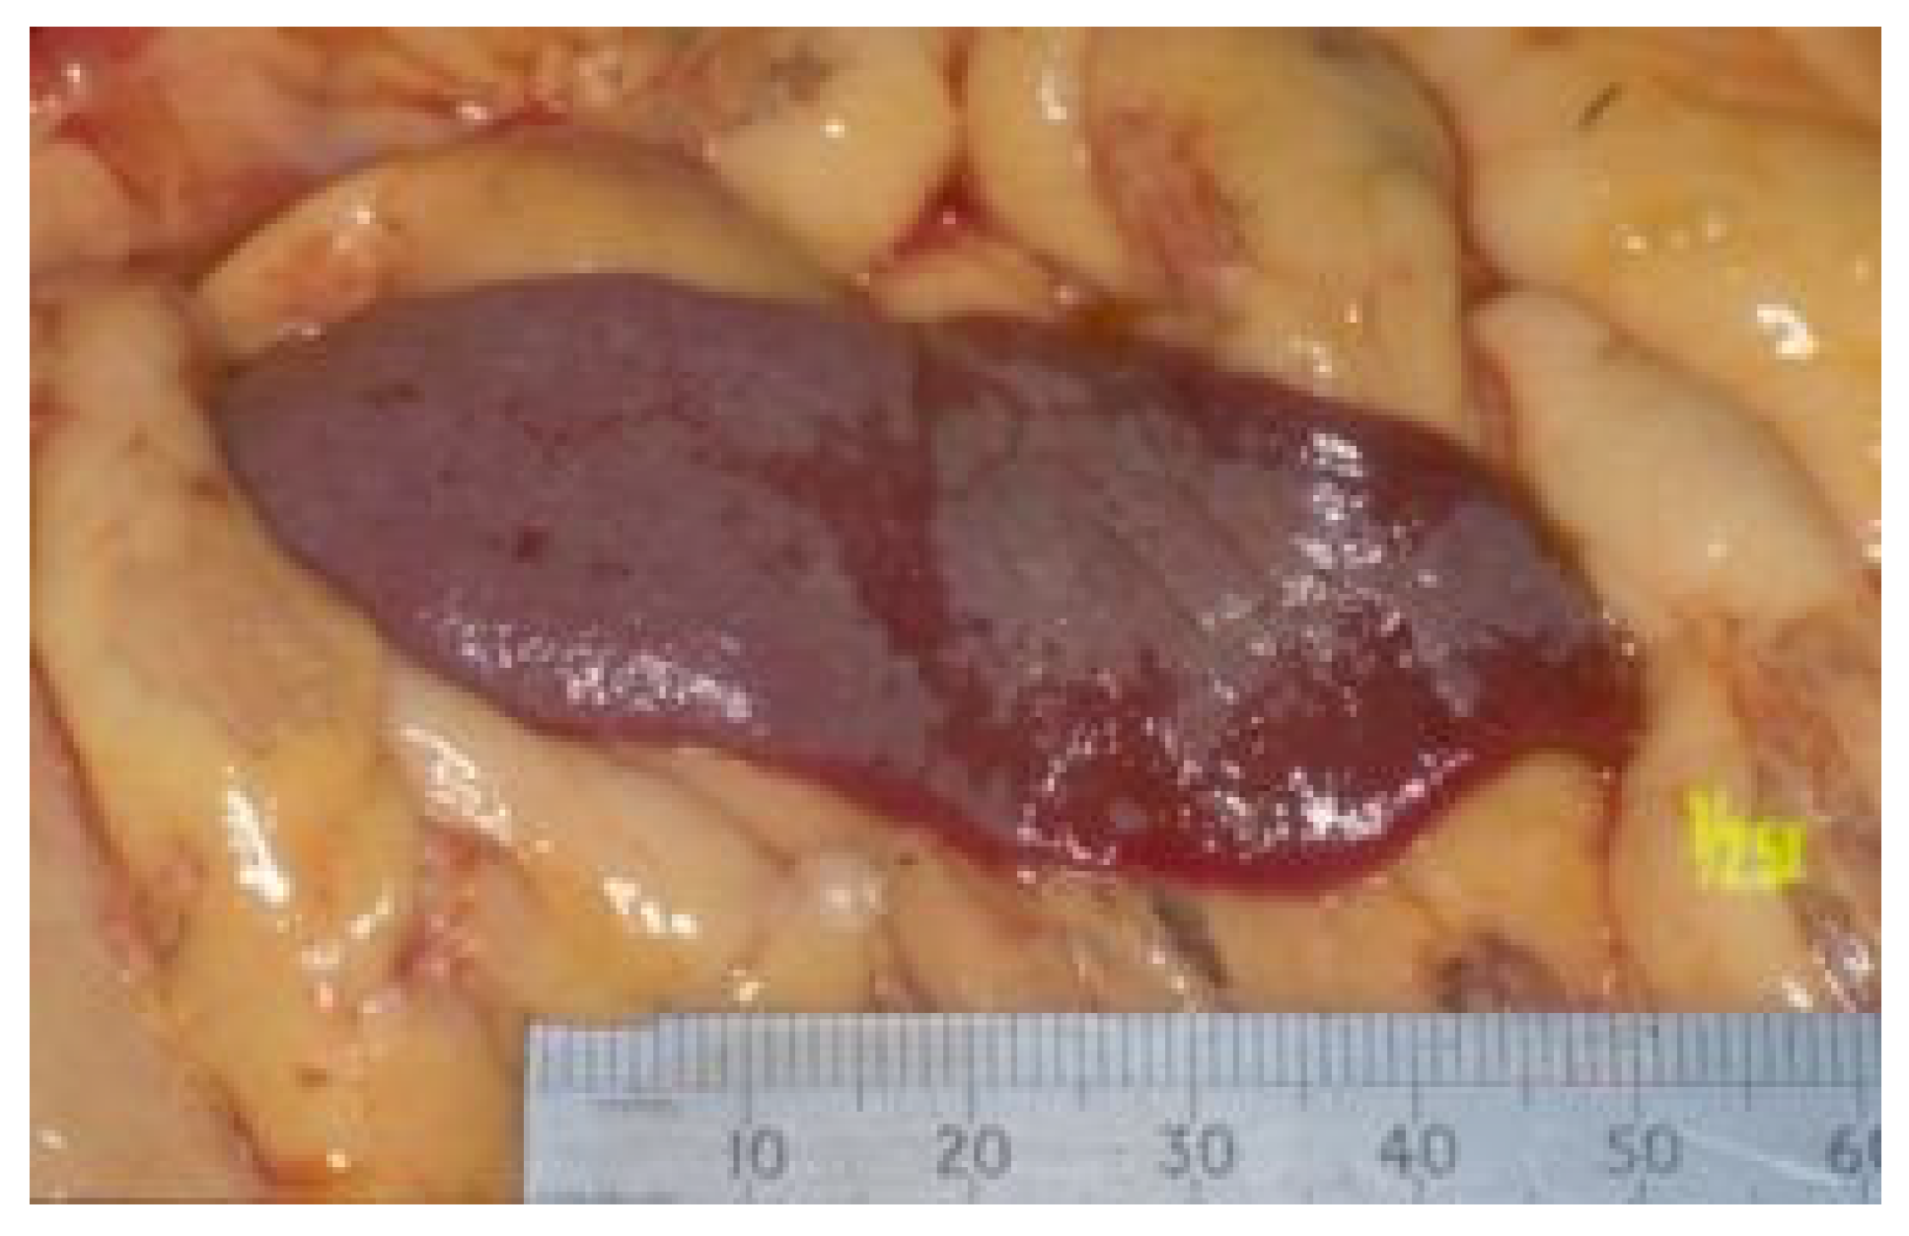

| Summary of Section 6: Clinical Signs FCoV Infection Cats with FCoV infection are usually subclinical, although occasionally diarrhoea and/or vomiting and poor growth (in kittens) can occur. FIP Cats that go on to develop FIP after FCoV infection present with varied clinical signs depending on the distribution of vasculitis (which can lead to effusions) and/or (pyo)granulomatous lesions (which can lead to mass lesions) in the body. Although effusive and non-effusive forms of FIP are often described, there is much overlap between these forms. Clinical signs of FIP can change over time, and therefore repeated physical examinations are important to detect newly apparent clinical signs; for example, an effusion can develop, or ocular changes can become visible on ophthalmoscopic examination. ABCD FIP Diagnostic Approach Tools [211] are available to help the vet assess clinical signs for FIP. Non-specific clinical signs include lethargy, anorexia, and weight loss (or failure to gain weight/stunted growth in kittens). A fever that is refractory to treatment is common. Effusions are common, especially in the abdomen, but pleural effusions and pericardial effusions are also seen, sometimes concurrently. When effusions are present, the disease progression is often quite fast, within a few days or weeks. When effusions are not present, FIP is often more difficult to diagnose and it also tends to be more chronic, progressing over a few weeks to months. Additional signs of non-effusive FIP depend on the organs affected but can include the central nervous system, eyes and/or abdominal organs (such as the liver, abdominal lymph nodes [especially mesenteric lymph nodes], kidney [including renomegaly], pancreas, spleen and/or gastrointestinal tract). These signs can also be present in cats with effusions. Abdominal lymphadenomegaly or intestinal masses (sometimes palpable), can occur. Jaundice can occur, more commonly in cats with effusions, but the degree of hyperbilirubinaemia is often not high enough to result in clinical jaundice. Occasionally, cats with FIP show skin signs. Neurological signs seen with FIP include ataxia (with varying degrees of tetra- or paraparesis), hyperaesthesia, nystagmus, seizures, behavioural and mental state changes, and cranial nerve deficits. Central vestibular clinical signs can include head tilt, vestibular ataxia, nystagmus, obtunded appearance, and postural reaction deficits. Fever was shown to be less common in cats with neurological FIP compared to those without neurological signs. FIP can also cause unilateral or bilateral uveitis. Clinical signs include changes in iris colour, dyscoria or anisocoria secondary to iritis, sudden loss of vision and hyphaema. Keratic precipitates can appear as ‘mutton fat’ deposits on the ventral corneal endothelium, and aqueous flare can occur. On ophthalmoscopic examination, chorioretinitis, fluffy perivascular cuffing (representing retinal vasculitis), dull perivascular puffy areas of pyogranulomatous chorioretinitis, linear retinal detachment, vitreous flare and fluid blistering under the retina can all be seen. Other less-common signs associated with FIP have included rhinitis and clinical signs associated with myocarditis. |

7.4.1. Routine Imaging: Ultrasonographic and Radiographic Findings

7.4.2. Advanced Imaging of the CNS: MRI and CT